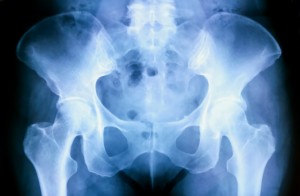

If any of this sounds familiar, you may want to consider hip replacement surgery (also known as “hip arthroplasty”). The hip is a ball-and-socket joint—where the top of the femur (thighbone) fits into the pelvis—and this procedure involves replacing one or both portions of the joint with artificial implants. Hip replacements can offer numerous benefits, including: